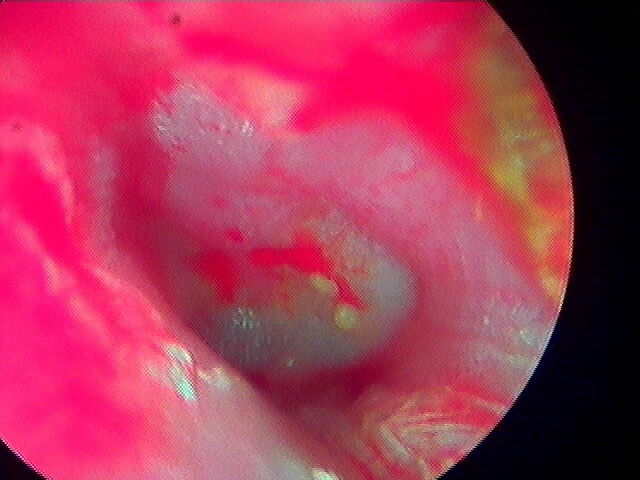

2/4 otite externe bactérienne phlegmoneuse

Quand l'otite externe bactérienne est avancée, elle créé une réaction inflammatoire importante avec sténose du CAE que j'appelle "phlegmoneuse" (non abcédée biensûr).

Cela va nécessiter une aspiration, la mise en place d'un tuteur ("pop") sorte d'éponge pour permettre le passage des gouttes, de revoir le/la patient·e à 72h pour retirer le pop et enfin voir le tympan.

À 72h après abaltion du pop, le conduit toujours inflammatoire mais ouvert permet de voir le tympan. Ici oreille droite.

Là oreille gauche.